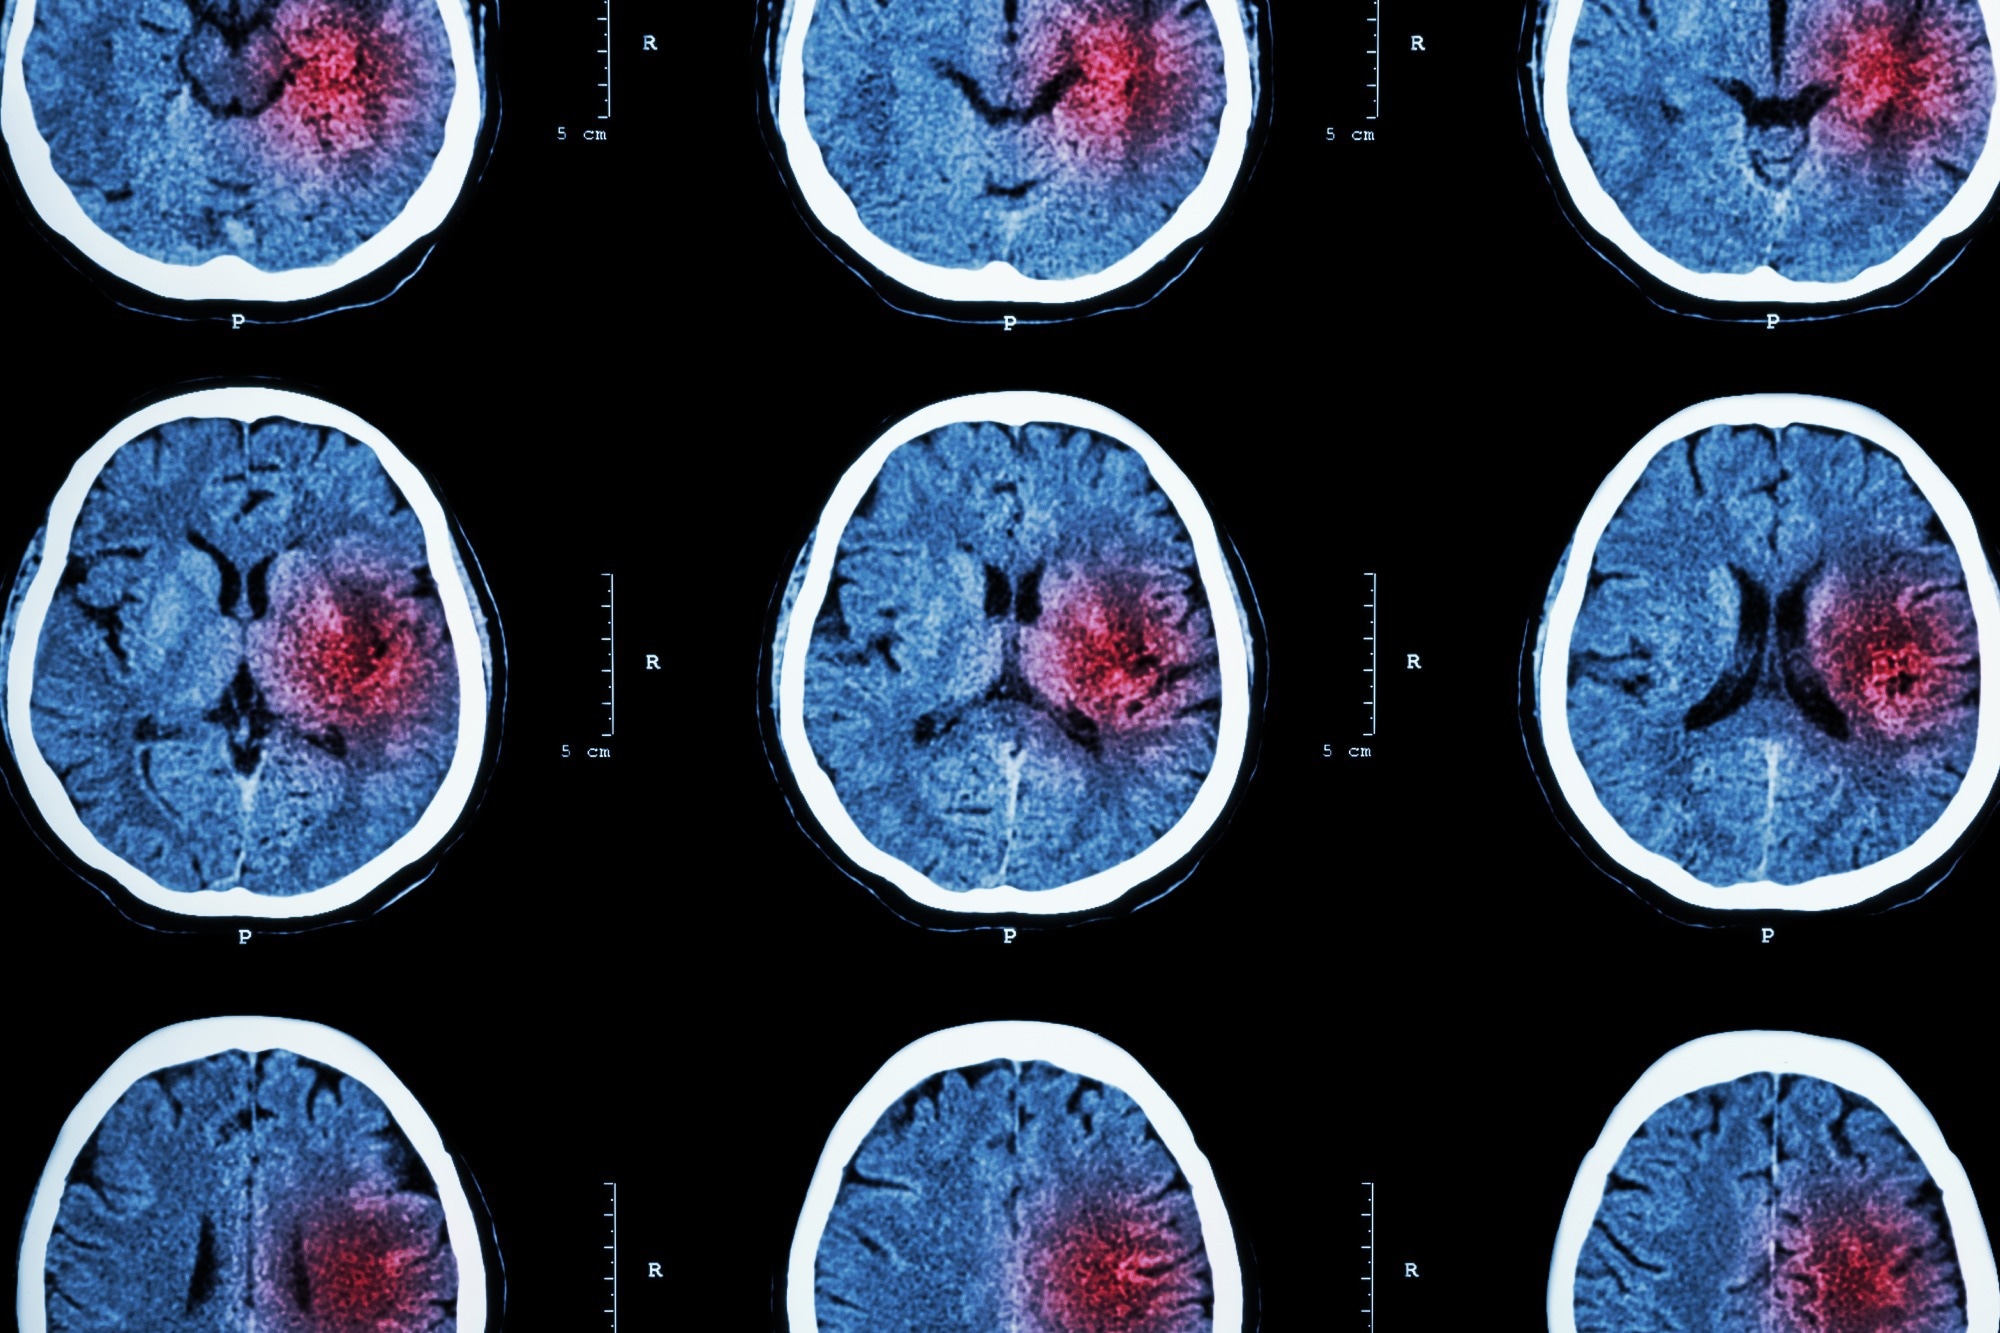

Image Credit: Inspiring/ShutterstockImage Credit: Inspiring/Shutterstock

A stroke occurs when a blood vessel that carries oxygen and nutrients to the brain is either blocked by a clot or bursts. Therefore, there are two types of stroke: ischemic and hemorrhagic.

Ischemic strokes – which are the most common and account for 87% of all cases – occur when a blood clot travels to a vessel in the brain and cuts off the blood supply. This prevents brain tissue from getting oxygen and nutrients, and brain cells can begin to die in minutes.

The other type of stroke, hemorrhagic, are often less common than ischemic strokes but can be more severe. These types of strokes are caused by a brain aneurysm burst or rupture of weakened blood vessels.